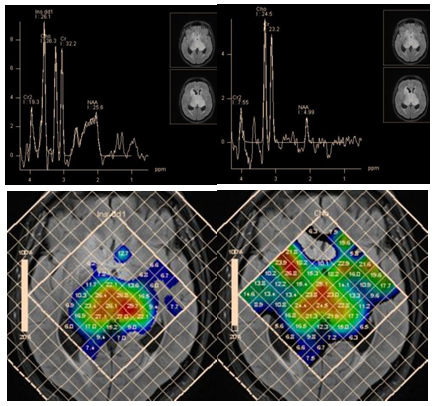

An increase of the myo-inositol level is typical for gliomas. The highest level of myo-inositol shows a relatively benign (grade II) astrocytoma. According to Riyadh et al.,45 the average value of Myo/Cr is 0.49 for benign and 0.33 to 0.15 for anaplastic glioblastoma.45,46 Spectroscopy also provides clinically valuable information for planning stereotactic biopsy (Figure 18), in evaluation of perifocal areas after invasive tumor removal, for radiation therapy planning (Figure 19), and in discrimination between radionecrosis and tumor recurrence (Figure 20). In all these cases, the highest concentration of choline (Cho/NAA and Cho/Cr ratio) is estimated.

Figure 18 Bilateral thalamic astrocytoma. PRESS, TE 30 ms (a) and PRESS, TE 135 ms (b) and map of myo-inositol (c) and choline (d) concentrations, for planning stereotactic biopsy. Histological analysis revealed anaplastic astrocytoma, though high myo-inositol concentration is more typical for grade II gliomas.

Figure 19 Maps of Cho concentrations in patients after removal of anaplastic astrocytoma without evidence of tumor invasion (a), and glioblastoma, with evidence of tumor invasion in the perifocal area (b).